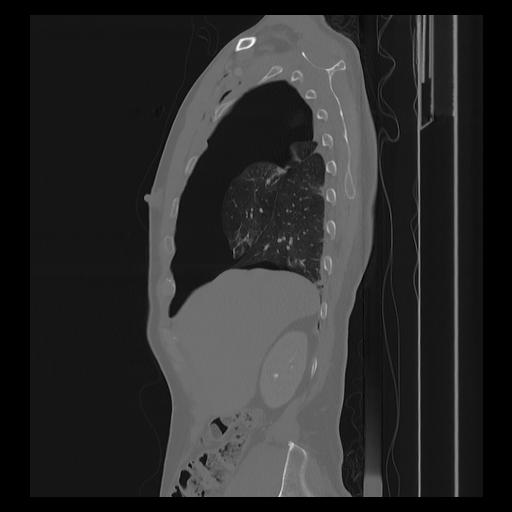

33 PULMON,CE,Sagittal,3.000,PULMON,Sagittal,